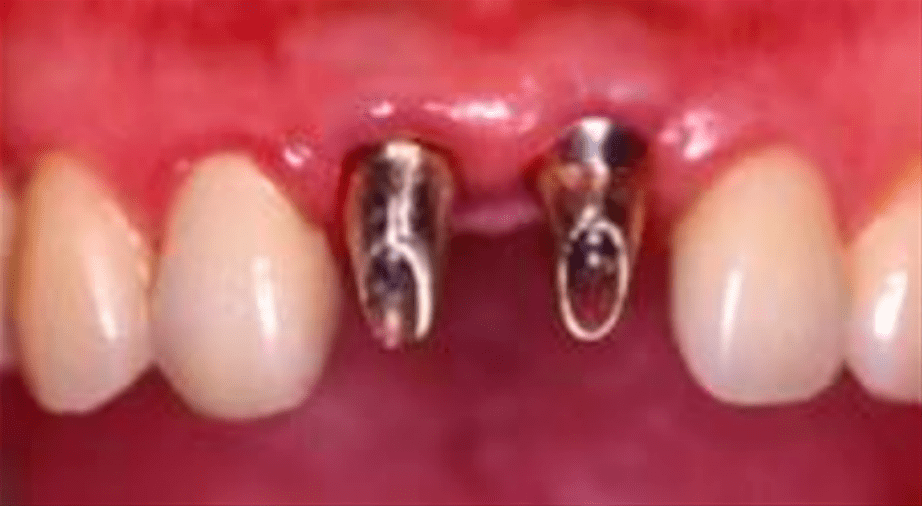

(图 / 患者种牙效果 本图版权为祯诺ZENOIS,由好牙医提供)